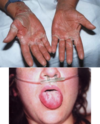

Dyshidrotic Eczyma

- pruritic, vesicular eruptions

- “tapioca” like

- bulla- pompholyx (small blisters on fingers, palms and feet)

- painful erosions/fissuring

- cause unknown

- Tx:

- high potency topical corticosteroids

- +/- oral steroids